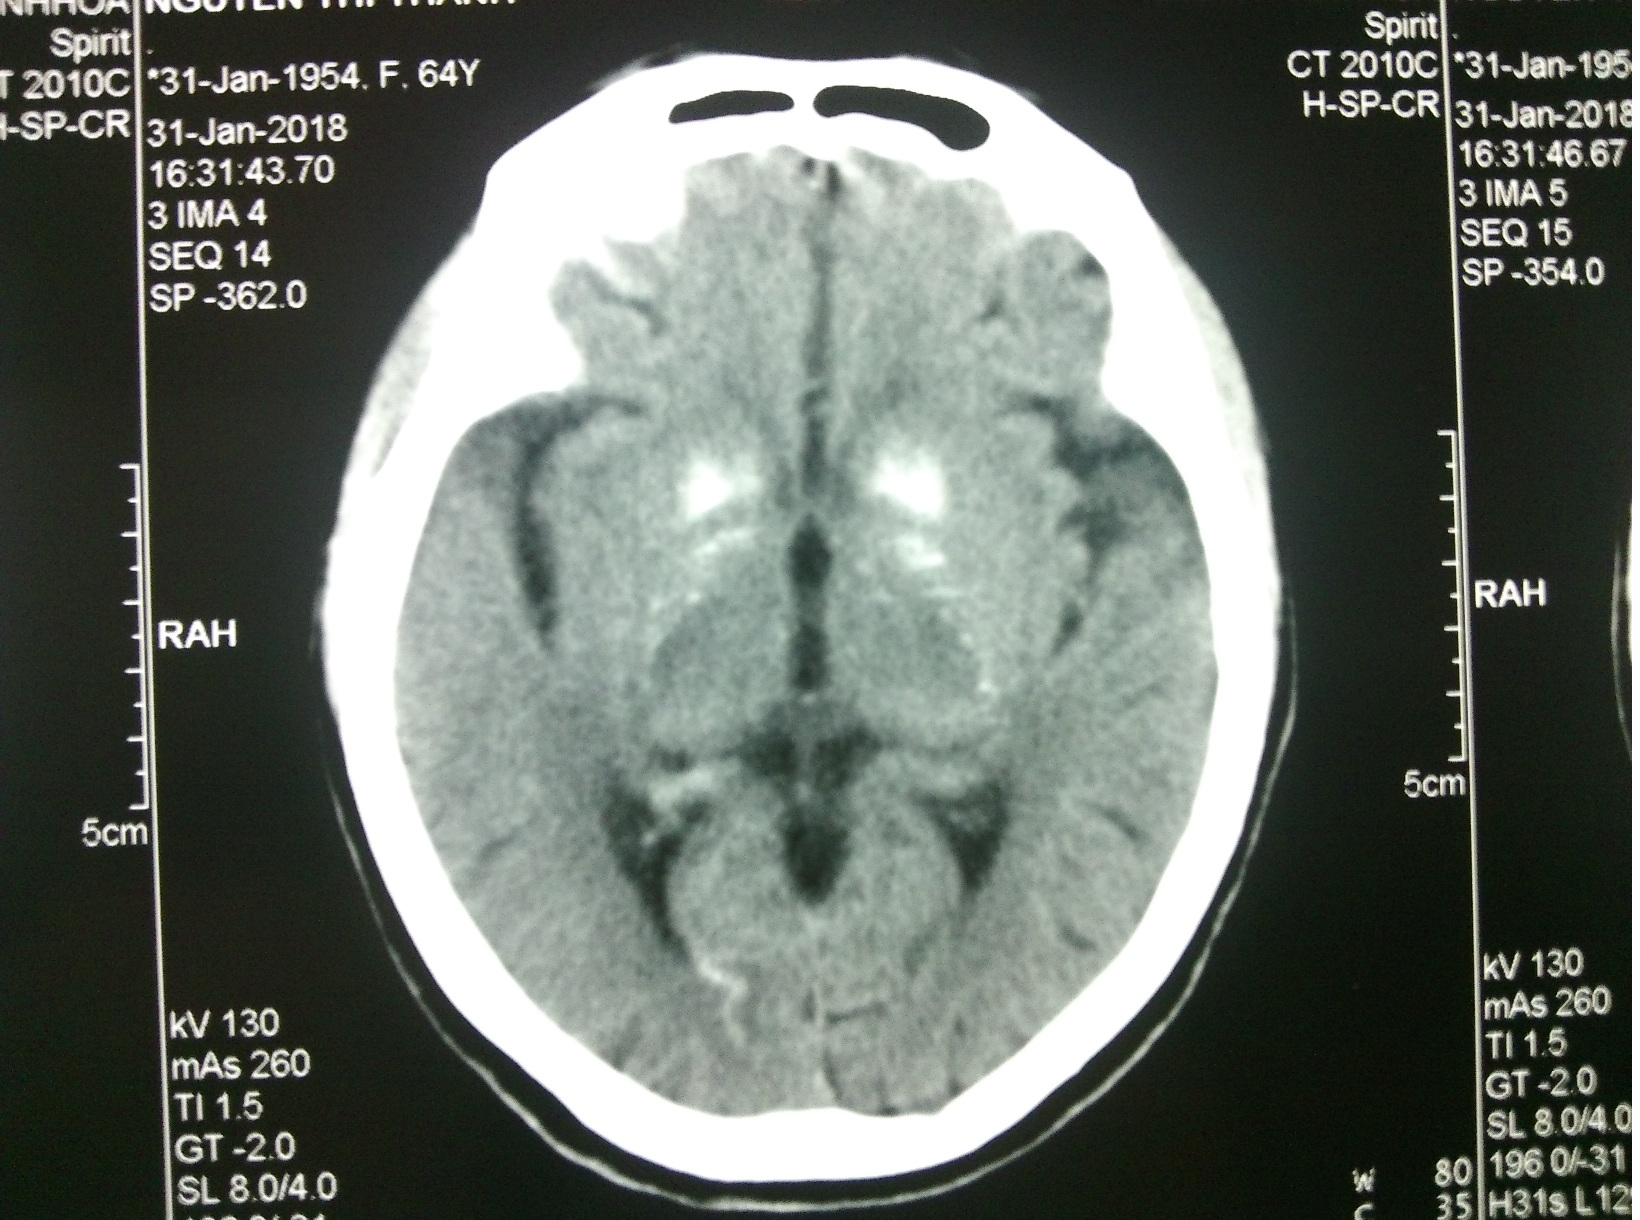

Chụp CLVT sọ não ngày 31/1/2018 hình ảnh vôi hoá nhân bèo, tiểu não đối xứng 2 bên

Chẩn đoán hội chứng Fahr dựa vào lâm sàng, hình ảnh não và loại trừ các nguyên nhân vôi hóa nội sọ khác. Vôi hóa đối xứng lan tỏa ở hạch nền, nhân răng, trung tâm bán bầu dục là đặc trưng và dễ thấy ở hội chứng Fahr.

Hình ảnh học: CT đầu là công cụ hiệu quả sàng lọc hội chứng Fahr, vôi hóa nội sọ có thể xảy ra 0.3 – 1.2% các trường hợp chụp CT đầu[2]

Trường hợp của chúng tôi có tiền căn mổ cắt tuyến giáp, không có tiền sử gia đình, các anh chị em trong gia đình đều bình thường, tiền sử lên nhiều cơn hạ calci huyếtvà đang điều trị parkinson 2 năm nay, canxi máu giảm nặng. Một bệnh nhân có biểu hiện triệu chứng tâm thần, một bệnh nhân biểu hiện triệu chứng hạ canxi máu. CT đầu vôi hóa đối xứng hai bên ở hạch nền, nhân răng, trung tâm bán bầu dục. Bệnh nhân được điều trị với bù canxi và vitamin D, magne, triệu chứng lâm sàng cải thiện và sau đó người bệnh xuất viện.